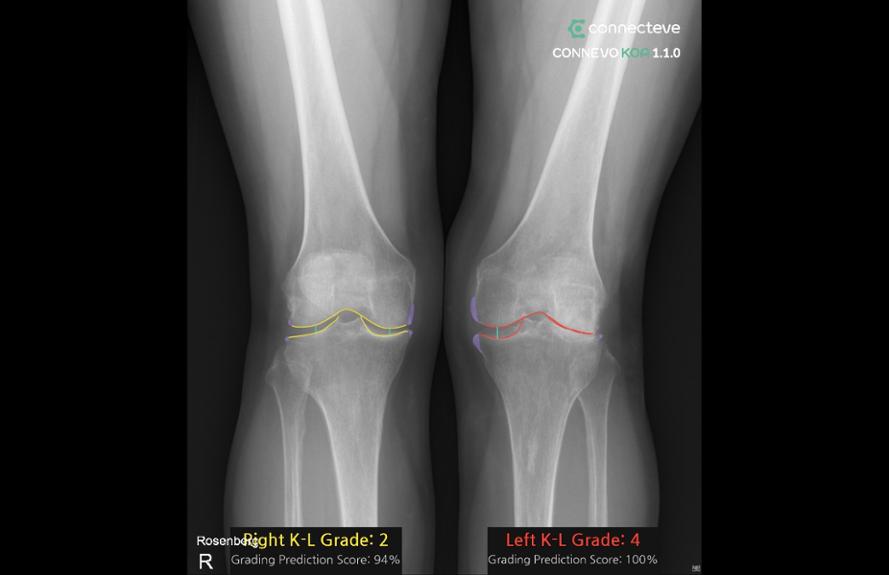

코넥티브의 CONNEVO KOA

코넥티브(G501)는 정형외과 수술의 디지털 전환을 선도하는 AI 의료기기 기업이다. 이번 전시에서는 무릎 엑스레이를 분석해 퇴행성 관절염을 자동 분류하는 ‘CONNEVO KOA’, 엑스레이 영상 지표를 자동 측정∙분석하는 ‘CONNEVO Metric’, 환자 상담을 지원하는 통합 플랫폼 ‘CONNEVO Suite’ 등 정형외과 AI 솔루션을 선보인다.